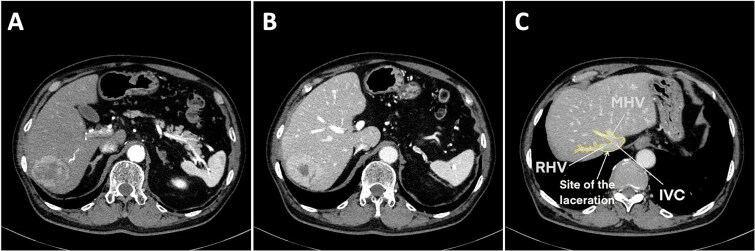

We report a case involving a hepatocellular carcinoma with massive bleeding from a large (retrohepatic inferior vena cava) RHIVC laceration during laparoscopic posterior sectionectomy, complicated by the exceedingly rare migration of surgical gauze into the left pulmonary artery (LPA). Hemostasis was achieved by manual compression and two anchoring Prolene sutures at both ends of the laceration, allowing effective RHIVC wall approximation. Given the low central venous pressure during hepatectomy, edge approximation significantly reduced bleeding and improved repair visibility. Postoperative imaging showed the gauze was lodged in the LPA, constituting an intravascular foreign body (IFB). The gauze was successfully retrieved via endovascular intervention without additional complications. Anchoring sutures with manual compression may be a helpful technique for managing a large RHIVC injury, and endovascular retrieval may provide a safe alternative to reoperation for a large IFB.